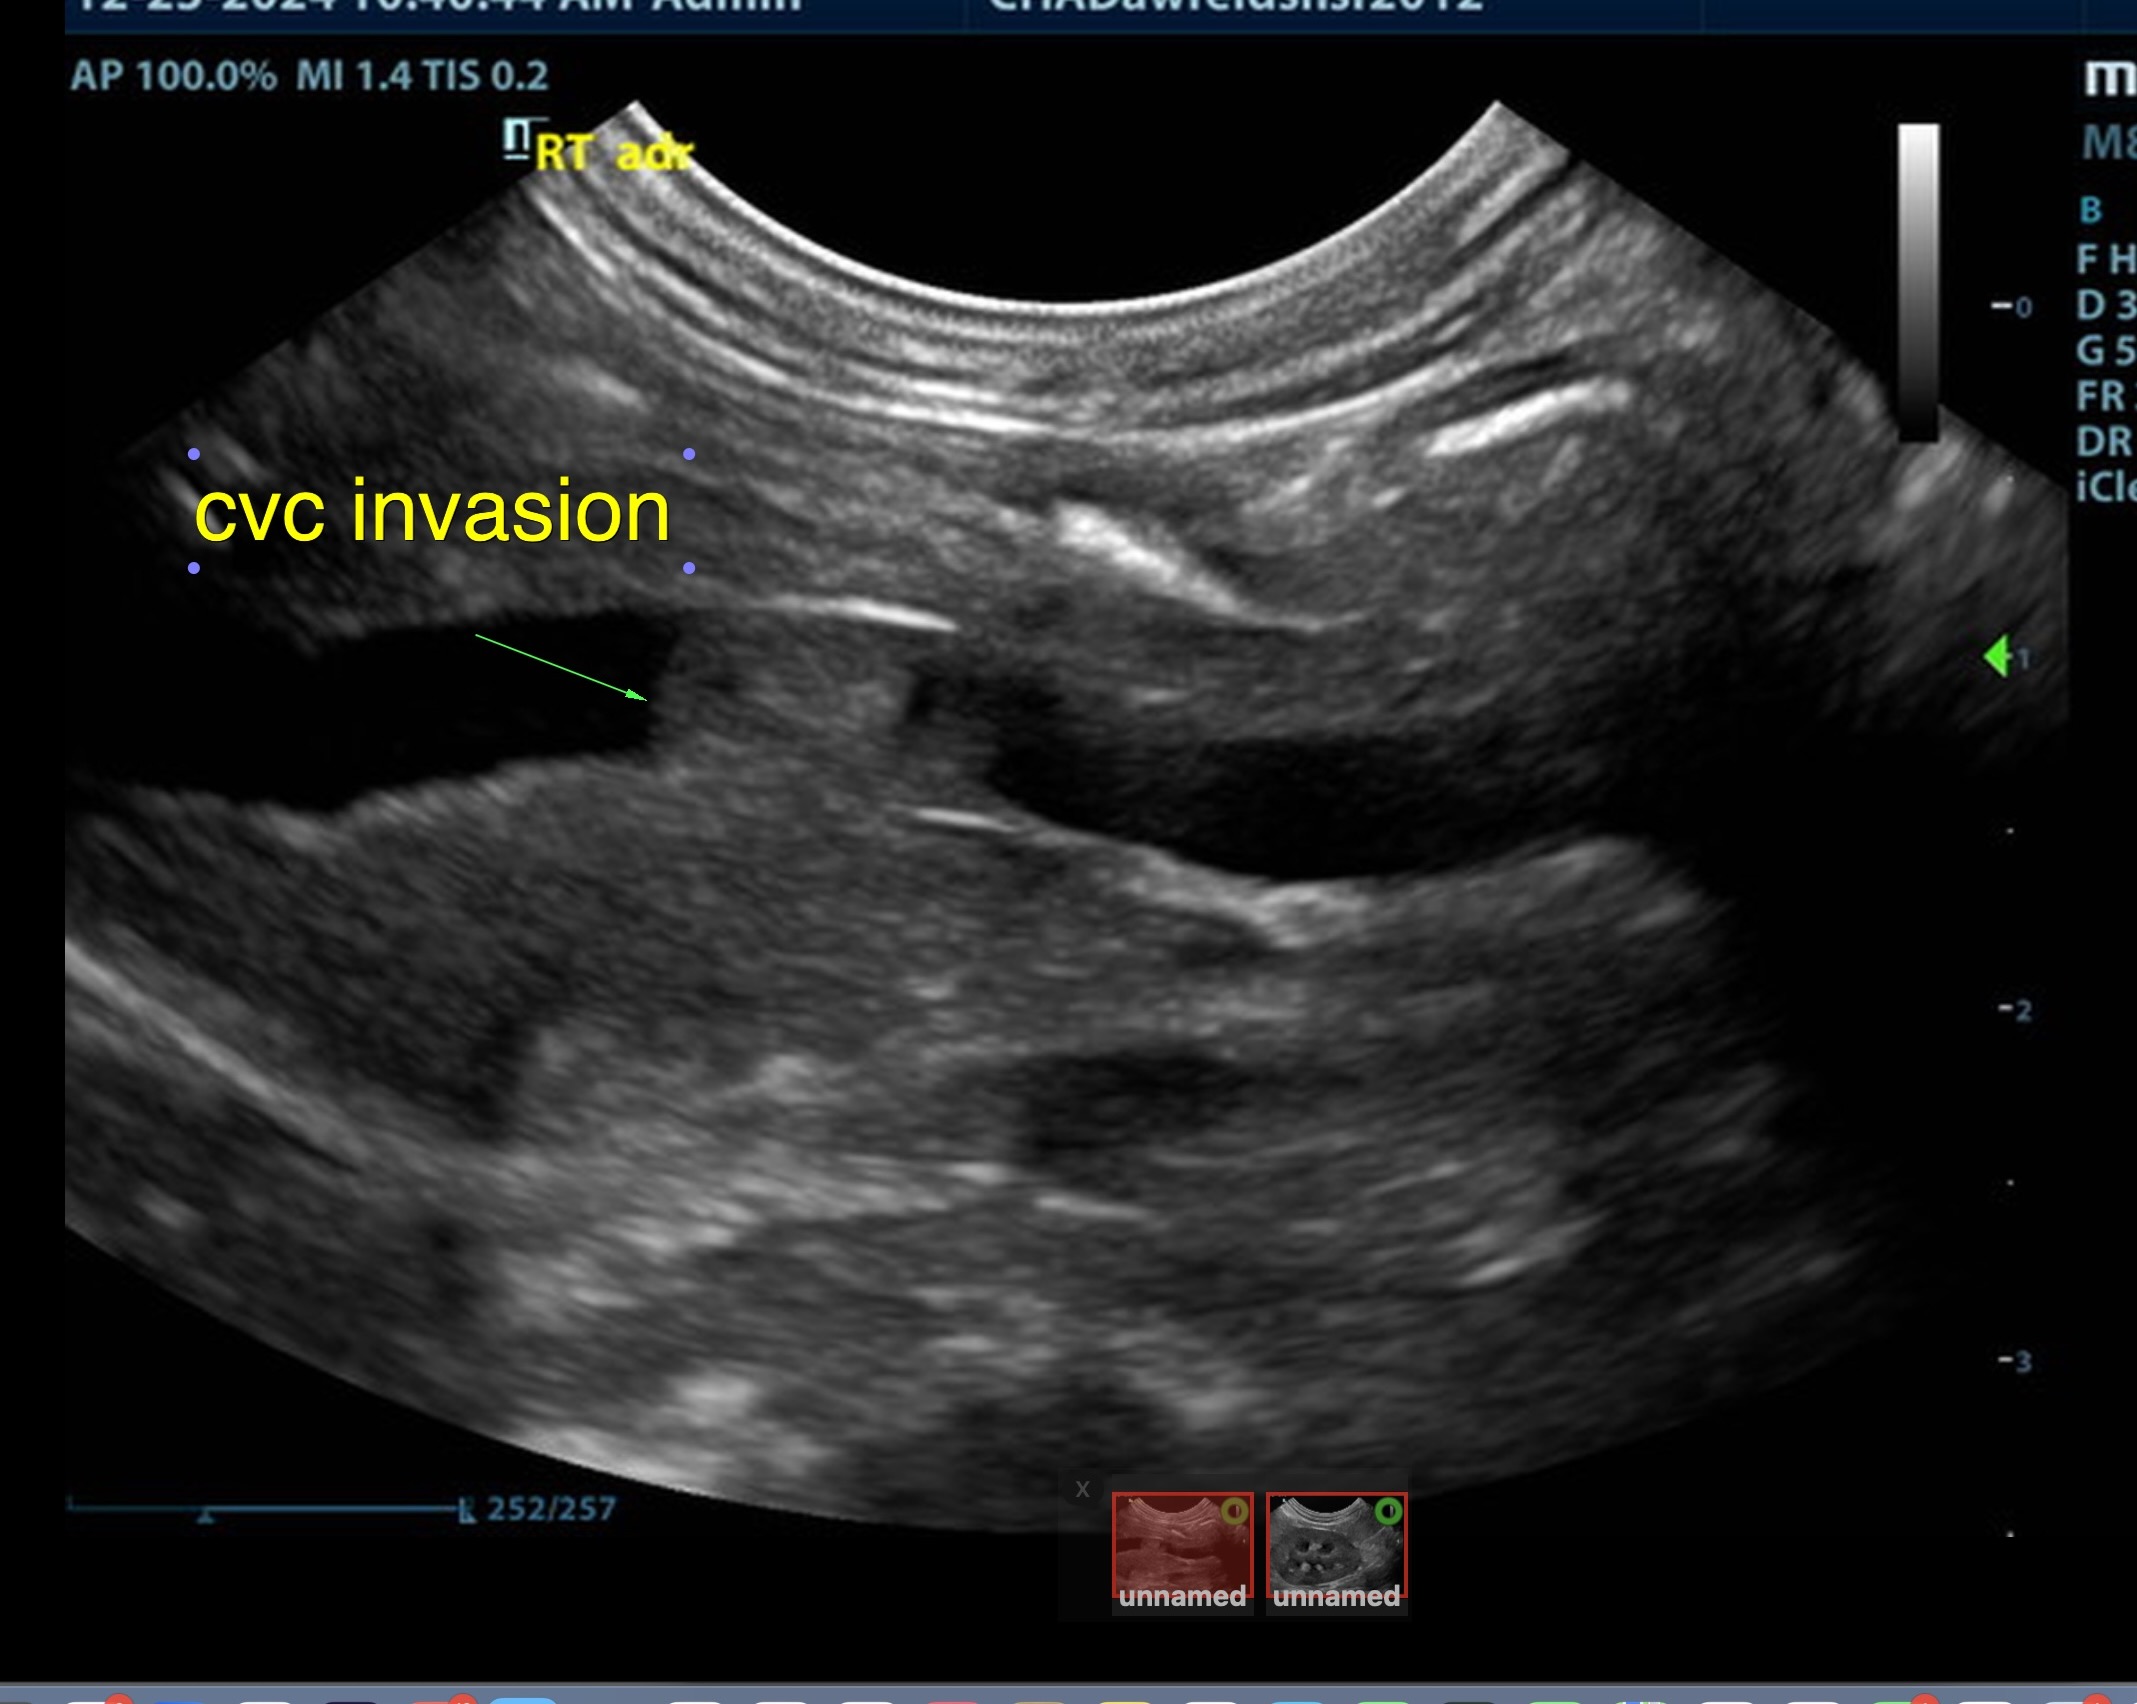

The right adrenal was enlarged and irregular, measuring 0.77 cm at the cranial pole and 0.30 cm at the caudal pole, with a caval invasion of 0.85 cm. Minor areas of mineralization noted. The left adrenal gland was recognized as normal. Mild variable GI thickening and echogenic submucosal changes. Some loss of renal curvilinear patterns regarding the capsule and cortico-medullary junction; increased echogenicity, mineralization.  Some hepatic parenchymal remodeling.

• Invasive right adrenal mass

Surgical consult warranted. The surgeon should be prepared for invasion of the vena cava at approximately 1.0 cm. Assessment of sodium to potassium ratio warranted. If hypokalemia present, aldosterone levels indicated. Serial blood pressures, chest radiographs warranted. No overt evidence of metastatic disease. The right adrenal pathology may not be overtly responsible for the weight loss. Malassimilation/maldigestion panel should be considered.